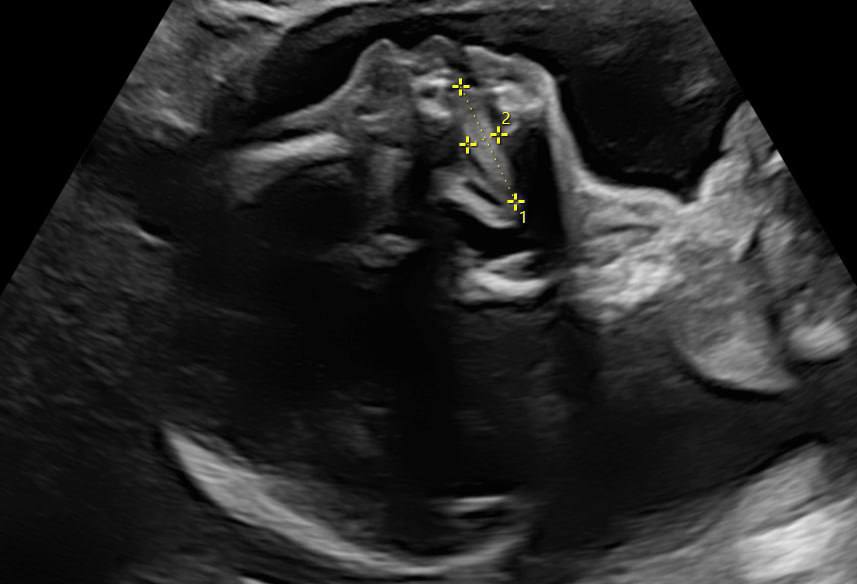

Программа анализирует параметры языка и черепа плода по оригинальной шкале, помогая объективизировать диагностику. Разработка призвана дополнить стандартные скрининги, что позволит раньше выявлять возможные отклонения.

Фото: пресс-служба оренбургского государственного медицинского университета